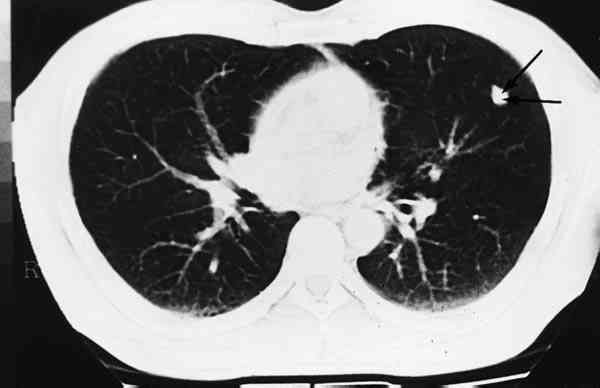

Figura 6

IMAGEN DE TAC PULMONAR DONDE SE EVIDENCIA LA LOCALIZACIÓN DE LA LESIÓN ANTERIOR.